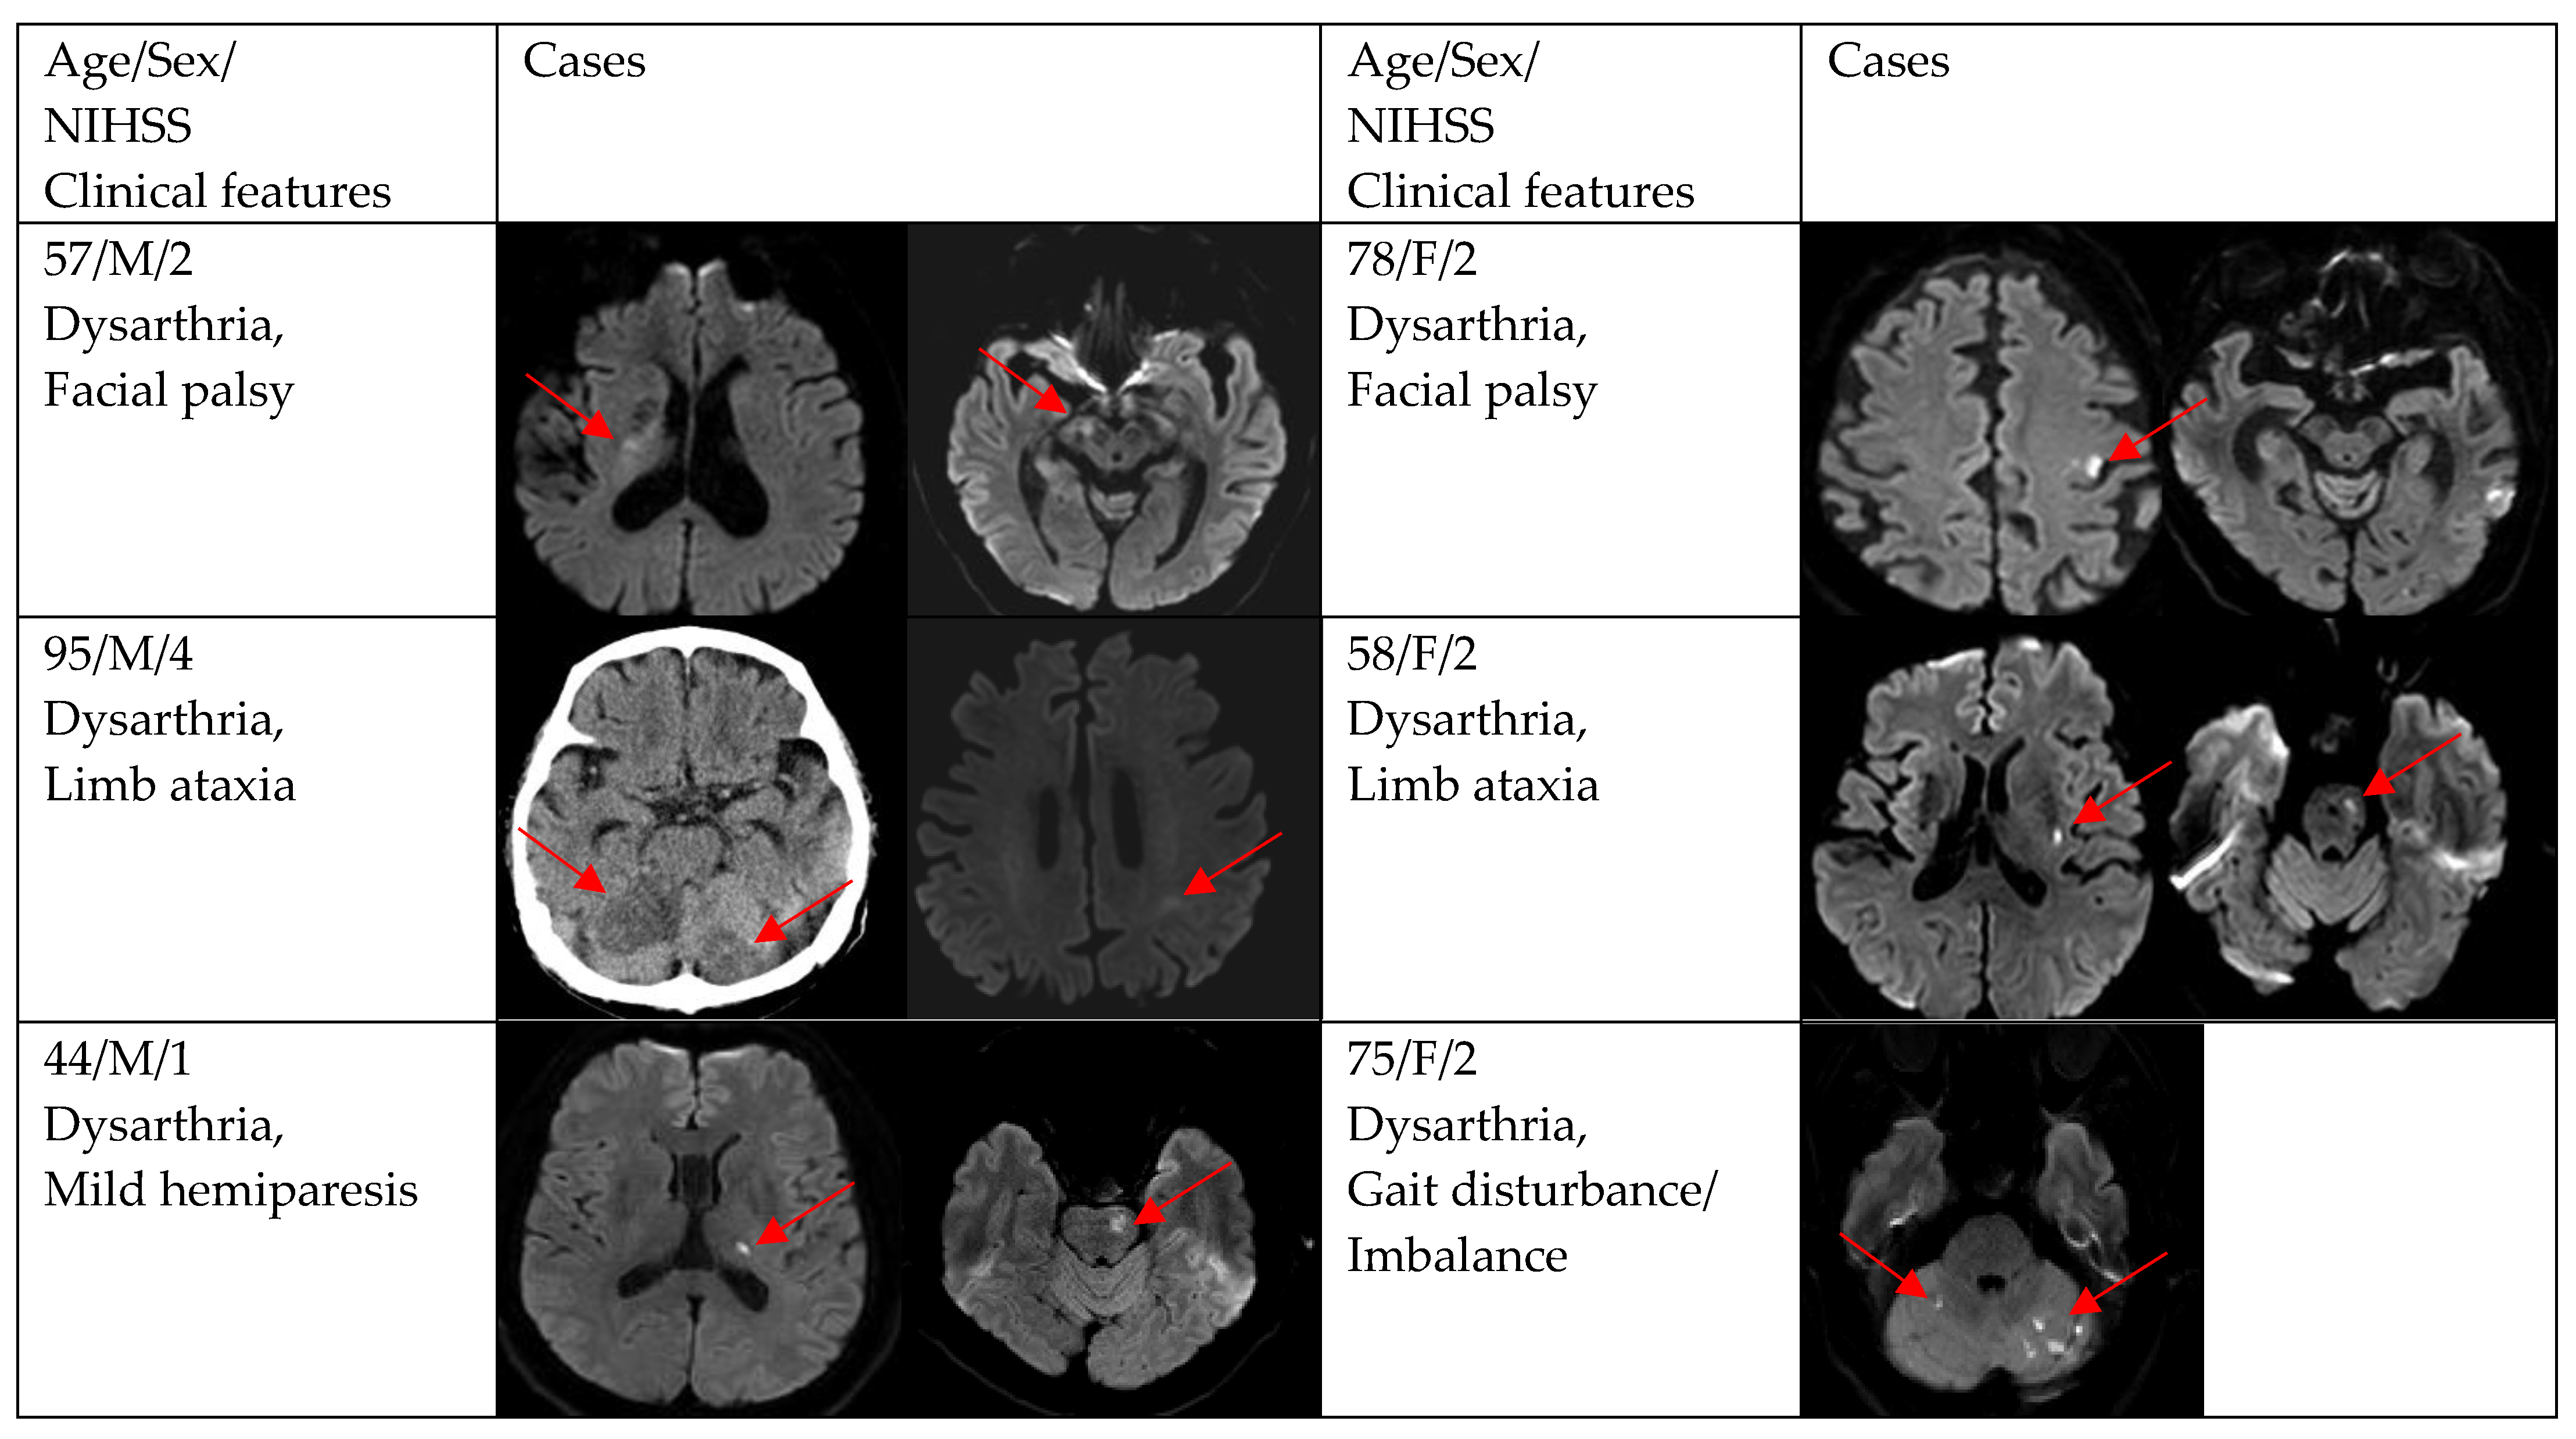

| Facial palsy | 8 (17.0) | 1 (7.7) | 7 (20.6) |

| Mild hemiparesis | 5 (10.6) | 2 (15.4) | 3 (8.8) |

| Limb ataxia | 3 (6.4) | 0 (0.0) | 3 (8.8) |